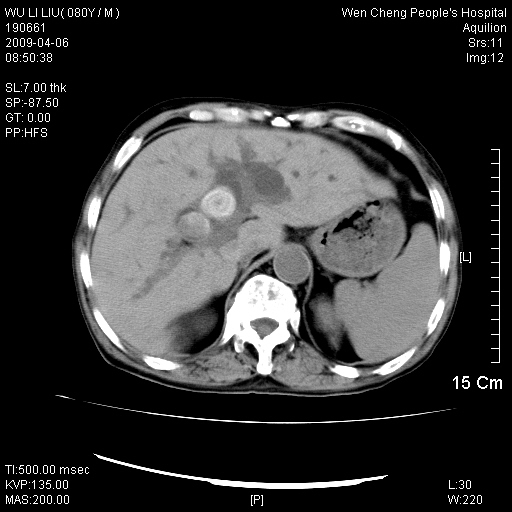

以下是引用zjzjr在2009-4-7 12:13:00的发言:[br]支持多发性转移瘤,右股骨颈骨折,腰椎亦有压缩性骨折.肝内胆管结石伴胆内外胆管扩张,左肾结石.

以下是引用liaoqiang在2009-4-7 8:44:00的发言:[br]考虑多发性骨髓瘤伴肝肺转移、肝内胆管结石、左肾结石、右股骨颈骨折。

以下是引用余辉在2009-4-7 8:52:00的发言:[br]椎骨及骨盆骨质疏松,骨破坏主要累及椎体,各骨破坏较广泛,各病灶边缘均较清晰锐利,血沉增快,白细胞增高.支持考虑多发骨髓瘤,建议查本尿周氏蛋白.[br]胆内胆管及左肾结石[br]右股骨颈骨折,考虑病理性